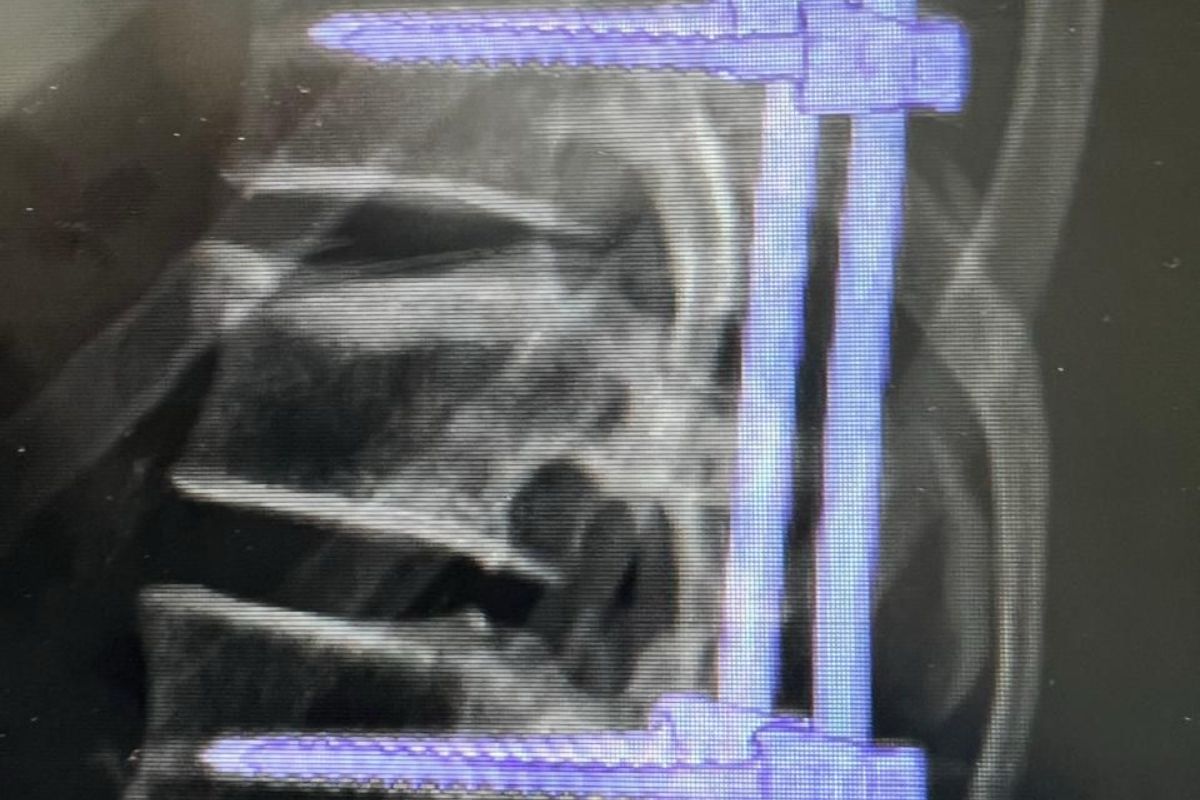

Впервые в городе Кульсары врачи провели транспедикулярную фиксацию пациенту с компрессионным переломом первого поясничного позвонка. Проведение такой операции подтверждает повышение уровня подготовки специалистов и укрепление материально-технической базы больницы.

Вмешательство выполнила команда врачей. В ее состав вошли заведующий травматологическим отделением Жакия Байзуллин, травматолог ортопед Нурдаулет Хусанов, анестезиолог-реаниматолог Саламат Жолдасбаев и травматолог-ортопед Абилхайыр Изимов. По словам Абилхайыра Изимова, операция пациенту 1989 года рождения прошла успешно благодаря слаженной работе специалистов. На данный момент состояние пациента оценивается как стабильное.